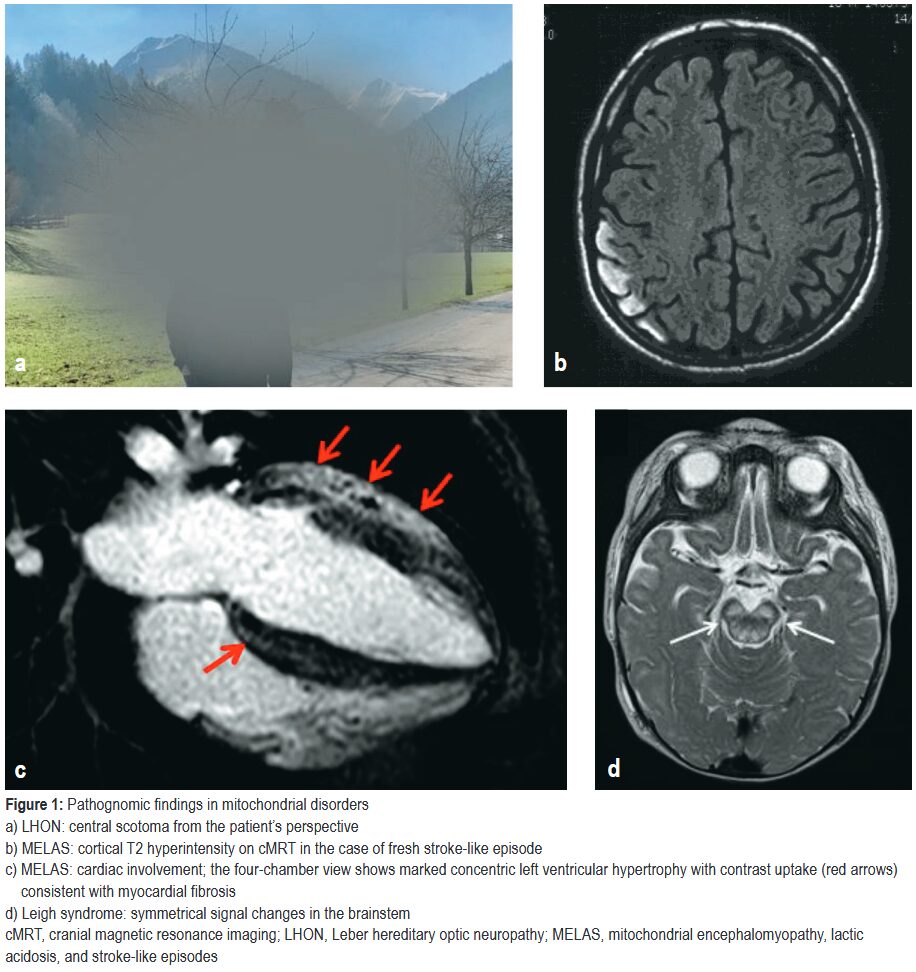

ミトコンドリア病、特にMELASの定義的特徴である。多くは40歳未満で発症するが、高齢発症も報告されている。頭痛・嘔気・視覚異常といった前駆症状に続き、けいれん・意識障害・局所神経脱落症状が出現する。

代表的な遺伝子変異:m.3243A>G(MELAS症例の最大80%を占める)・POLG変異

画像所見:MRIでは特定の血管支配領域に一致しない大脳皮質および皮質下白質の病変が特徴的。

主に小児期のミトコンドリア病で最も一般的な病型であるLeigh症候群は、軽症例では成人期まで生存することがある。これらの患者は、感染症などを契機として、眼球運動障害・嚥下障害・構音障害・中枢性低換気といった亜急性の脳幹機能不全を呈することがある。

代表的な遺伝子変異:MT-ATP6、SURF1など多数

レーベル遺伝性視神経症(LHON)の典型的な症状である。通常、片眼の無痛性かつ進行性の中心視力障害として発症し、数週間から数ヶ月以内にもう一方の眼にも同様の症状が現れる。

脳卒中様エピソード:頭痛・嘔気嘔吐・脳症・焦点性てんかん発作・精神症状に引き続いて神経脱落症候が出現する。通常10~20代で発症。

原因遺伝子:m.3243A>G変異が症例の最大80%を占める。

MRI:脳卒中様病変が通常血管支配領域に対応せず、皮質や皮質下白質に現れる。MRSでは病変部・脳室内・病変部以外のいずれでも乳酸ピークがみられる。病変は数日~数週あるいは数か月かけて拡大し、その後は消失することもあるが、皮質の層状壊死・グリオーシス・萎縮をきたすことが多い。

画像所見:脳幹機能障害では、髄質の非対称病変や基底核の対称性T2高信号が見られることがある。